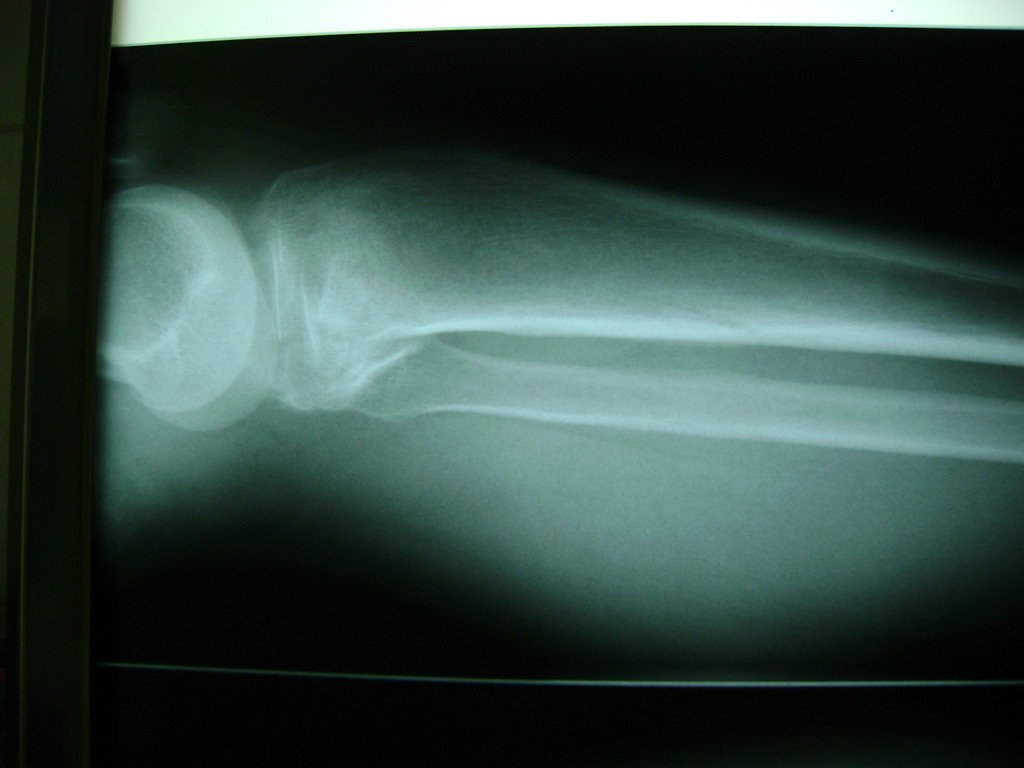

Cirugía de Rodillas